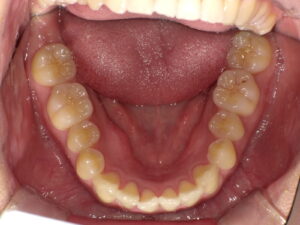

下の歯並びだけ直すことはできる?矯正の選択肢

▶ 軽度なら「部分矯正」でOKな場合も

- 前歯だけが少しガタついている

- 噛み合わせに大きな問題がない

このようなケースであれば、マウスピースやワイヤーで下の歯だけを整える部分矯正が可能です。

▶ 噛み合わせの乱れがあるなら「全体矯正」推奨

下の歯だけ矯正しても、上下のバランスが崩れていれば再び乱れる可能性が高いです。

このような場合は、**上下のかみ合わせまで含めた矯正計画(全体矯正)**が適しています。